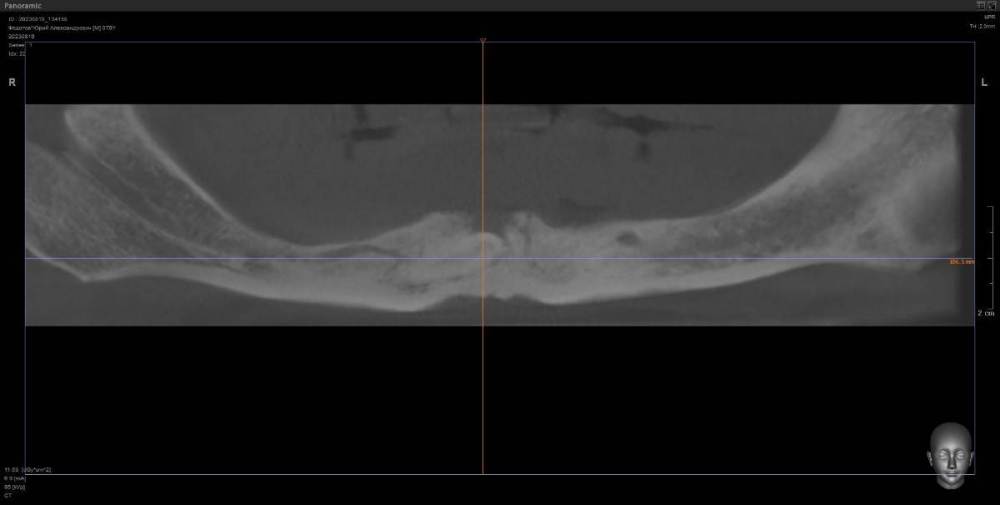

kriokov Опубликовано 10 августа, 2023 Поделиться Опубликовано 10 августа, 2023 ретенция клыка справа. кость 1 тип. Выход нерва почти по вершине. Сьемник не держится. М- 70 лет. Здоров. Нужен совет по установке имплантата справа под локатор, без удаления клыка. Слева штатно. Ссылка на комментарий

annda Опубликовано 13 августа, 2023 Поделиться Опубликовано 13 августа, 2023 (изменено) Предположу, что это должны быть как раз первые 4- 6 мм имплантата , корональная его часть( как при синус лифтинге том же) . в данном кейсе ( на втором соезе, что показан) совсем же другая ситуация. В этом ракурсе можно срез посмотреть не через коронку клыка, а через апикальную треть корня, над которым как раз и лежит массив своей губчатой кости.Посмотреть, сколько его там. А самый первый срез чем не устраивает ?Там область за местом выхода СНП или я не понимаю чего-то? Изменено 13 августа, 2023 пользователем annda Ссылка на комментарий

kriokov Опубликовано 13 августа, 2023 Автор Поделиться Опубликовано 13 августа, 2023 10 часов назад, annda сказал: А самый первый срез чем не устраивает ?Там область за местом выхода СНП или я не понимаю чего-то? Думаю првильно понимаете, это более менее позиция, 6 часов назад, TIGER сказал: 2 импланта под 30 гр м.ю,балочка между ними,и никакого гемора с клыком и локаторами как вариант, да + Ссылка на комментарий